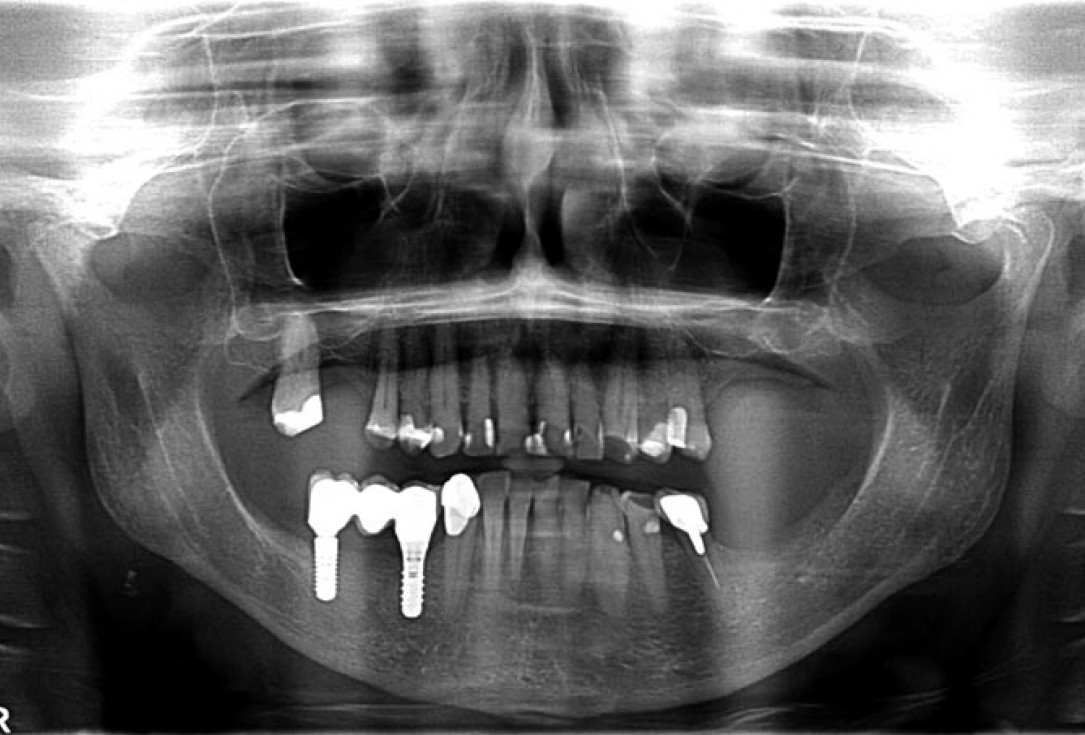

02/14 - Preoperative radiological situation

Block augmentation with maxgraft® in the mandible - PD Dr. Dr. F. Kloss